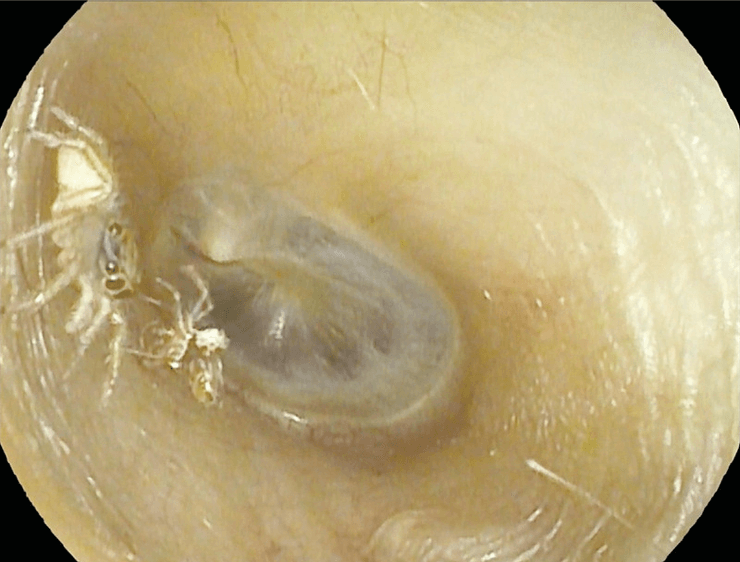

Врачи обнаружили маленького паучка, который передвигался по ушному каналу | Фото: The New England Journal of Medicine

Женщина обратилась в специализированную клинику. Там врачи обнаружили маленького паучка, который передвигался по ушному каналу. Он отбросил свою старую кожу, который лежал рядом. В апреле врачи с помощью трубки отсосали паука и экзоскелет, говорится в отчете о случае, опубликованном в среду в New England Journal of Medicine.

"Она не чувствовала боли, поскольку паук был очень маленьким. Он всего 2-3 мм", — сказал доктор Тенгчин Ванг, соавтор отчета и директор отоларингологического отделения Тайнаньской муниципальной больницы.

Он сказал, что написал отчет из-за новизны случая: он уже видел муравьев, мотыльков, тараканов и комаров в ушах людей, но никогда не видел насекомых, которые бы линяли внутри слухового прохода. Доктор призвал людей обращаться к врачу, если у них возникают подобные симптомы.